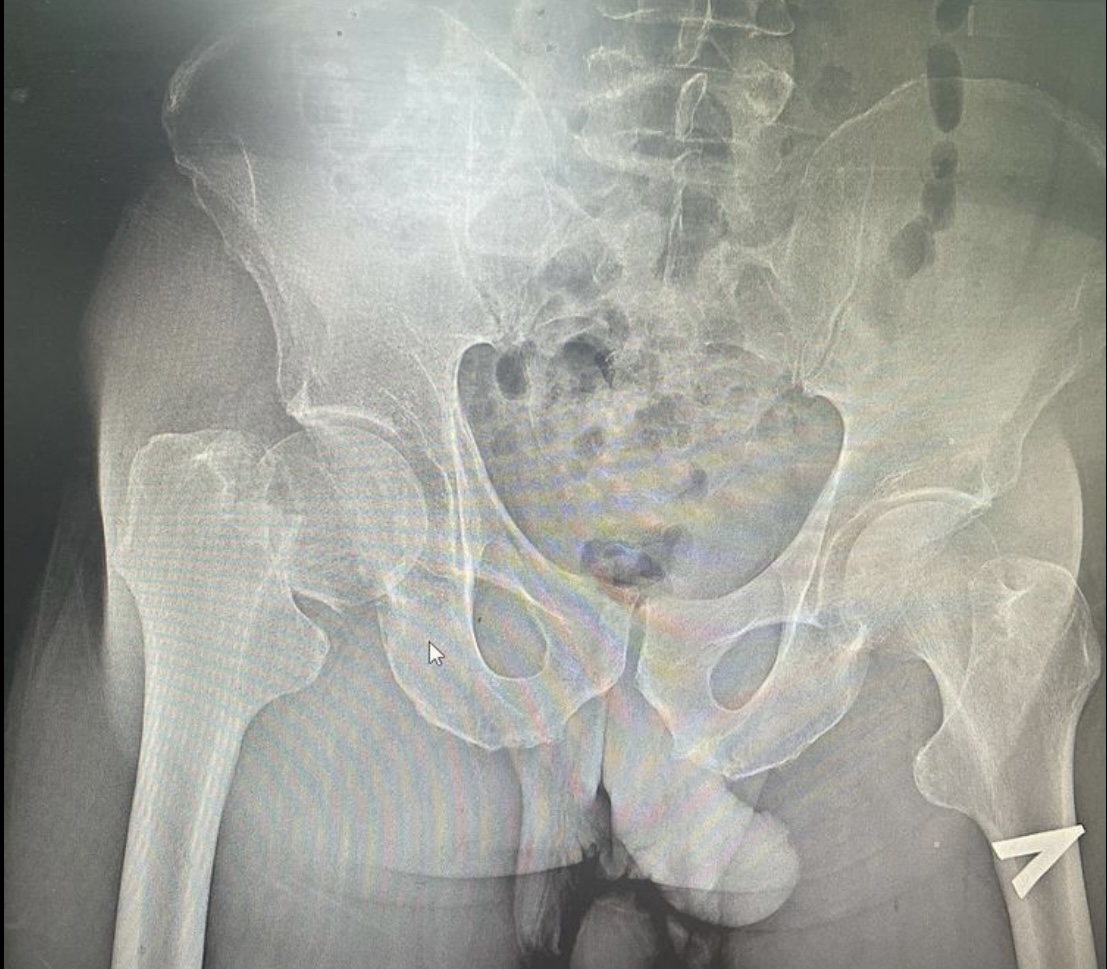

Представляем два рентгенснимка: в первом случае – 50-летний пациент с субкапитальным переломом шейки бедренной кости. Выполнено тотальное эндопротезирование тазобедренного сустава эндопротезом бесцементной фиксации.

Во втором случае - пациент 84 года с переломом шейки бедренной кости. Выполнено тотальное эндопротезирование тазобедренного сустава эндопротезом цементной фиксации.